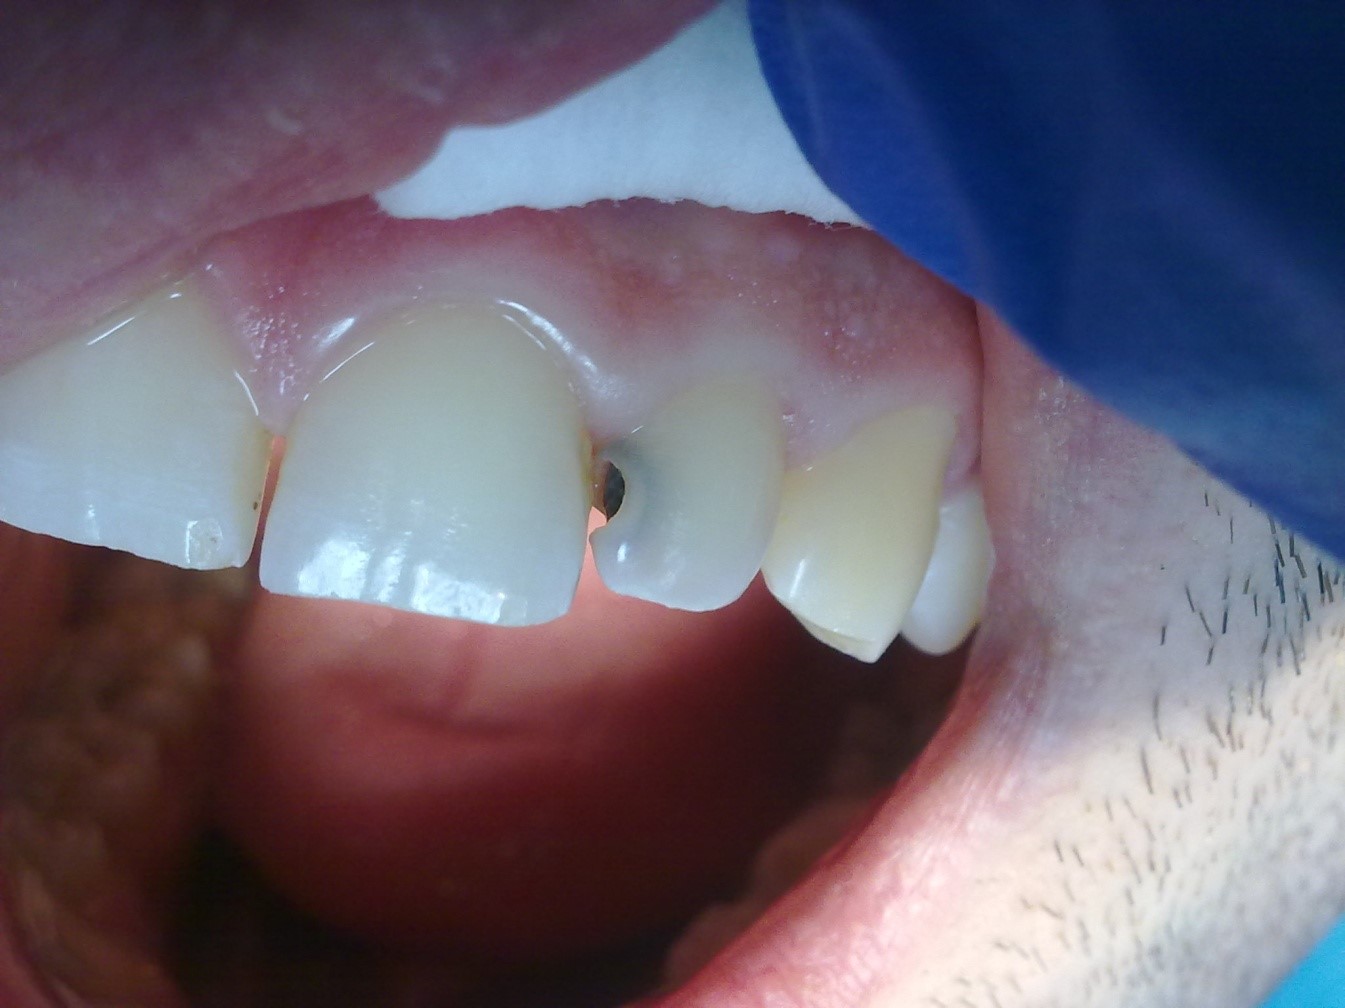

На фотографии изображён поверхностный кариес, который относится к необратимым процессам развития заболевания эмали зубов. Если кариес на ранней стадии можно лечить аппликациями фтора и кальция, то поверхностный кариес удаляется только при помощи пломбировочных материалов и использования бормашины.